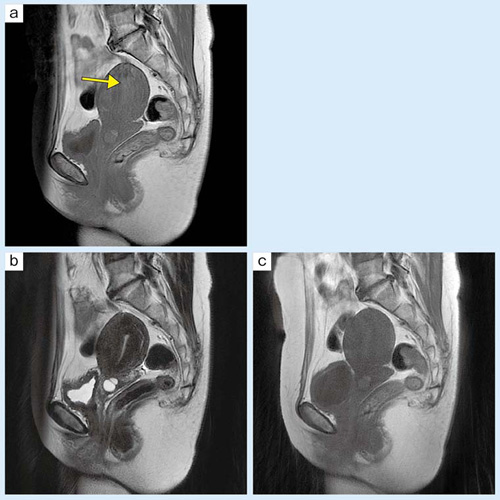

■症例3:子宮頸部嚢胞

FSEで見られるアーチファクト(a →)がRADAR-FSE(b,c)で抑制されている。

a:T1WI,FSE,FOV:260mm,TR/TE:500/10,FA:90°,スライス厚:6mm,撮像時間:2:08

b:T2WI,RADAR-FSE,FOV:260mm,TR/TE:5000/117,FA:90°,スライス厚:6mm,撮像時間:2:45

c:T1WI,RADAR-FSE,FOV:260mm,TR/TE:500/10,FA:90°,スライス厚:6mm,撮像時間:1:58